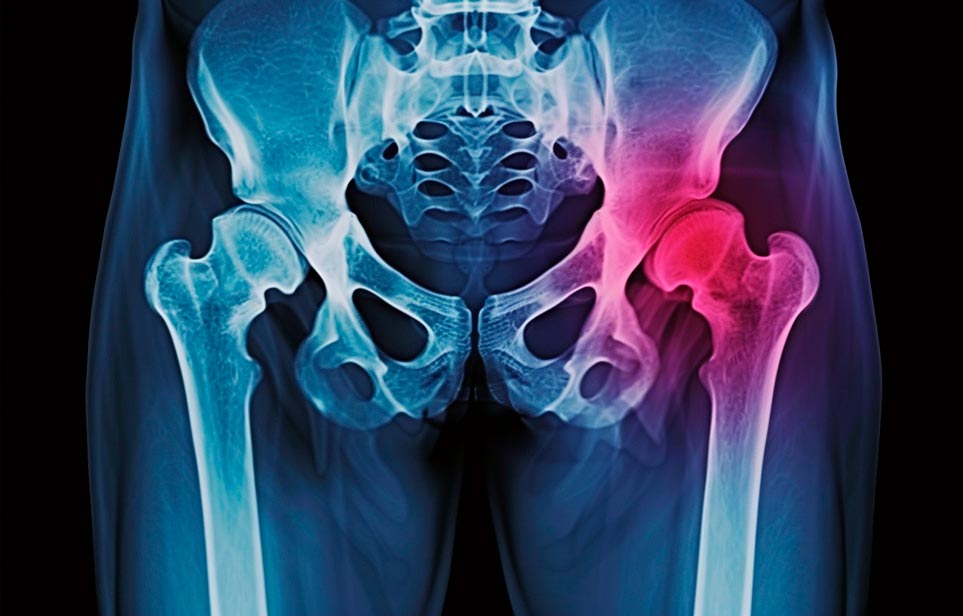

Эффективная и профессиональная реабилитация после перелома шейки бедра в Новомосковске осуществляется по демократичным ценам лучшими специалистами современной медицинской клиники «Заботливые люди» с применением персонального подхода к каждому пожилому человеку с такой тяжёлой травмой бедренной кости ноги. В процессе осуществления такой специализированной услуги все наши пациенты имеют возможность получения качественного и достойного обслуживания, эффективного восстановления. Лучший дом престарелых позаботиться о Вашем близком человеке.

Такая травма в большей части случаев возникает у граждан преклонного возраста. При её появлении на протяжении длительного времени сохраняются болевые и неприятные ощущения в области паха, при которых серьёзно ухудшается качество жизни, возникает множество последствий для его жизни и здоровья.

По какой симптоматике можно определить перелом шейки бедра?

Выявить его можно по возникновению следующей тревожной симптоматики:

- Визуально повреждённая нога сокращается на несколько сантиметром из-за сокращения мышц.

- Стопа выворачивается наружу.

- В лежачем положении человек не может поднять ногу.

При такой симптоматике важно незамедлительно обращаться к специалистам для получения всей необходимой помощи, терапии и восстановления после перелома шейки бедра. Если не оказать помощи старику, то это приведёт к гноению, инвалидности, иным видам осложнений.